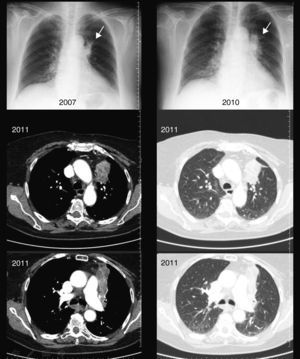

Caso 3Mujer madrileña de 84 años sin hábitos tóxicos, que durante su infancia (entre los 0 y 25 años) se sirvió para uso doméstico habitual de infiernillos y de cocina de carbón. Posteriormente trabajó en el servicio doméstico, sin exposición posterior a biomasa. En 2006 fue estudiada por infiltrado triangular en la zona anterior del lóbulo superior izquierdo (fig. 1) confirmado por TAC de tórax con lenta resolución, por lo que se realizaron 2 broncoscopias que mostraron edema y estenosis de embocaduras de los segmentos del culmen del lóbulo superior izquierdo con mucosa de color negro-violáceo (fig. 2), junto con el crecimiento de enterobacterias y de Haemophilus. influenzae en respectivas endoscopias. Se trató según determinó el antibiograma, con leve mejoría radiológica; no hay seguimientos posteriores ni datos de la evolución. La histología de las biopsias no evidenció malignidad, sin concluir el diagnóstico. En 2010 fue remitida nuevamente a estudio por infiltrado en el segmento anterior de lóbulo superior izquierdo (fig. 1) que no mejoró tras un ciclo de Cefditoren. Una nueva TAC mostró masa-atelectasia heterogénea en el segmento anterior del lóbulo superior izquierdo que englobaba el bronquio segmentario produciendo la obstrucción del mismo, con pérdida de volumen del lóbulo superior izquierdo (fig. 2), y una adenopatía paratraqueal derecha de 1cm. Ante la sospecha neoformativa se realizó una nueva broncoscopia (fig. 2), que mostró una masa vegetante negra que estenosaba la embocadura anterior y ápico-posterior de lóbulo superior izquierdo y que, al biopsiarla, mostró una mucosa con corion fibroso y abundante antracosis sin datos de malignidad. Los cultivos fueron negativos. No se aislaron bacilos tuberculosos, por lo que no se instauró tratamiento específico.